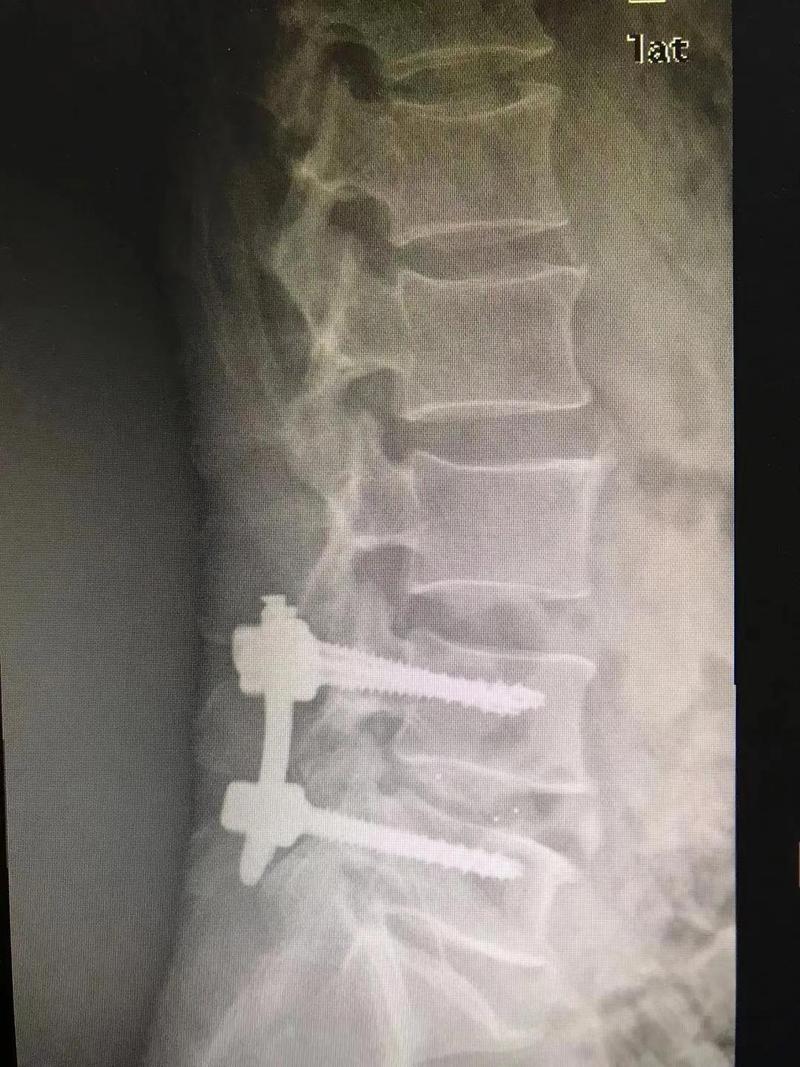

术前

经过周密的术前评估及患者意愿,张昊主任决定利用UBE技术为叶先生进行治疗。

术后

与开放外科手术相比,UBE技术只需切两个1cm大小的切口,通过肌间隙进入,创伤明显减少,术中出血少。对椎旁肌肉损伤较小,且能够最大程度地保留完整的脊柱结构,维持了术后脊柱的稳定。术后效果立竿见影,并发症少,恢复快,对术后活动几乎没有影响。

■ 腰椎融合术

是通过植入一些器械(如融合支架或者椎弓根螺钉)使上下两个锥体融为一体,不能再相对活动。一般来说不作为首选手术,只适用于以下情况:腰椎间盘突出症伴明显的慢性轴性腰背痛;巨大椎间盘突出、腰椎不稳;复发性腰椎间盘突出,尤其是合并畸形、腰椎不稳或慢性腰背痛的情况。